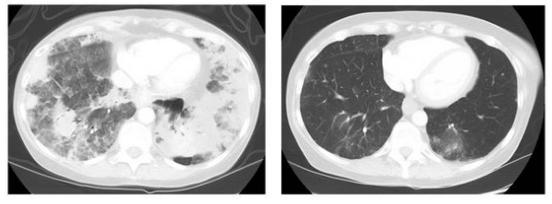

如图所示,在易瑞沙特罗凯耐药患者中,完全缓解和部分缓解占比达60%左右,效果非常显著。

左图为服用AZD9291之前的肺部CT影像,右图为服用八周AZD9291之后的CT影像,可以看到肺部的肿瘤细胞明显收缩凋亡,患者情况极大好转。